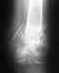

Наадо сделать КТ. И оперировать - надо восстанавливать форму суставной поверхности, т.е. поднять просевший мыщелок. Дефект заместить ауто- или алломатериалом. Фиксировать пластиной или аппаратом. Если в той больнице, где пациент сейчас, такие операции на потоке не делаются, то лучше перебраться куда-то в более продвинутое место.